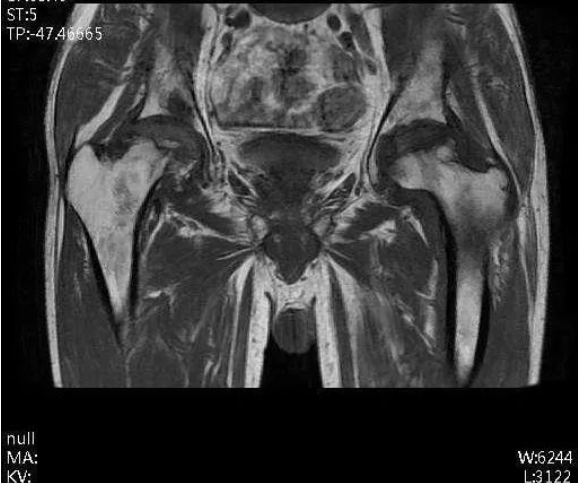

入院后,通过完善X线片、三维CT、MR等相关检查。发现周先生双侧股骨头坏死,尤其右侧股骨头严重变形,相关检查结果提示周先生的股骨头坏死已非常严重,双侧均达到Ficat分期Ⅳ期,右下肢较对侧缩短2cm。双侧髋关节旋转活动受限,右侧髋关节活动受限较重,双侧“4”字试验(+)。

术前MR